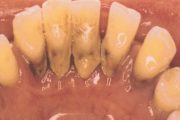

Sümptomid:

- igemed veritsevad (19)

- igemed punetavad (21)

- ige on paistes (mädapunn)

- igemed on tursunud/vohavad (17)

- puudulik suuhügieen (5)

- igemepealne hambakivi (5)

- igemealune hambakivi (4)